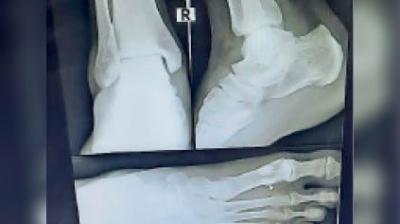

बुजुर्ग महिला का पैर चार जगह से टूटा, दर्दनाक हादसे से मचा हड़कंप

दिल्ली| ग्रेटर नोएडा वेस्ट की सुपरटेक ईकोविलेज एक सोसायटी में बिजली जाने से लिफ्ट 13वीं से आठवीं मंजिल पर जाकर गिर गई। लिफ्ट में सवार 65 वर्ष की बुजुर्ग महिला...